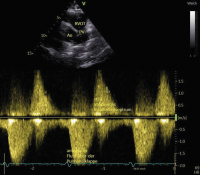

Abbildung 4: Parasternale kurze Achse über Aorta und PK; Z. n. OP bei TOF, schwere PI. Im Farbdoppler sieht man nur in der frühen Diastole den roten Rückfluss (rot = zum Schallkopf) bis weit in den Pulmonalishauptstamm bzw. sogar bis in die PA-Äste. ACHTUNG: Da der Rückfluss nur in der frühen Systole stark ausgeprägt ist, kann er leicht unterschätzt werden.